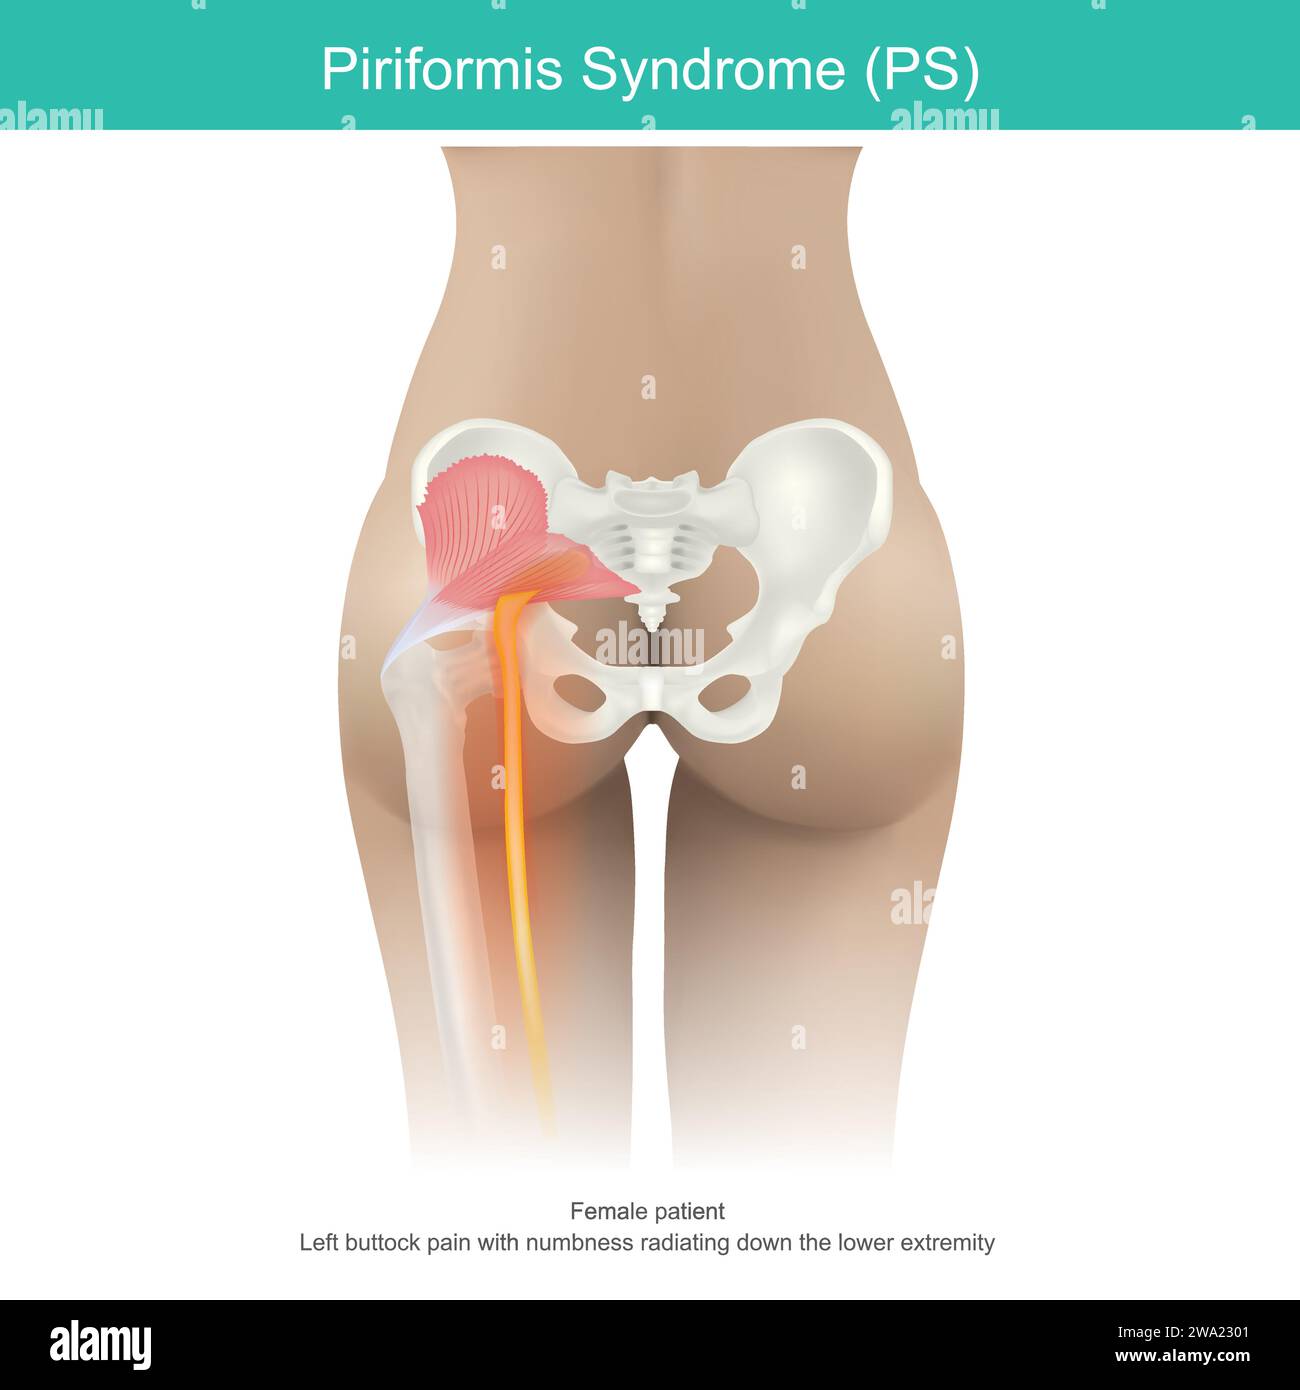

Sindrome di Piriformis. una condizione in cui la compressione nervosa nei muscoli, situata nella regione natica provoca dolore natico e fino alla coscia nel wo Illustrazione Vettorialehttps://www.alamy.it/image-license-details/?v=1https://www.alamy.it/sindrome-di-piriformis-una-condizione-in-cui-la-compressione-nervosa-nei-muscoli-situata-nella-regione-natica-provoca-dolore-natico-e-fino-alla-coscia-nel-wo-image591345329.html

Sindrome di Piriformis. una condizione in cui la compressione nervosa nei muscoli, situata nella regione natica provoca dolore natico e fino alla coscia nel wo Illustrazione Vettorialehttps://www.alamy.it/image-license-details/?v=1https://www.alamy.it/sindrome-di-piriformis-una-condizione-in-cui-la-compressione-nervosa-nei-muscoli-situata-nella-regione-natica-provoca-dolore-natico-e-fino-alla-coscia-nel-wo-image591345329.htmlRF2WA2301–Sindrome di Piriformis. una condizione in cui la compressione nervosa nei muscoli, situata nella regione natica provoca dolore natico e fino alla coscia nel wo